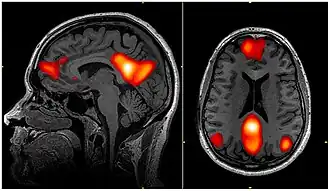

![]() fMRI scan showing regions of the default mode network; the dorsal medial prefrontal cortex, the posterior cingulate cortex, the precuneus, and the angular gyrus | |

In neuroscience, the default mode network (DMN), also known as the default network, default state network, or anatomically the medial frontoparietal network (M-FPN), is a large-scale brain network primarily composed of the dorsal medial prefrontal cortex, posterior cingulate cortex, precuneus and angular gyrus. It is best known for being active when a person is not focused on the outside world and the brain is at wakeful rest, such as during daydreaming and mind-wandering. It can also be active during detailed thoughts related to external task performance.[3] Other times that the DMN is active include when the individual is thinking about others, thinking about themselves, remembering the past, and planning for the future.[4][5] The DMN creates a coherent "internal narrative" central to the construction of a sense of self.[6]